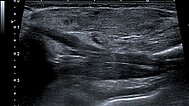

Power Doppler imaging at the end of the 8th month of life shows not only an increase in volume of the subcutaneous tumor, but also a further marked increase in perfusion (color-coded in orange).

The corresponding B-scan ultrasound at the end of the 8th month of life shows not only the increase in volume but also markedly increased hypoechoic parts of the tumor. This corresponds to areas of cell proliferation and is a characteristic of an infantile hemangioma in the proliferation phase, but may also occur in other vascular tumors.